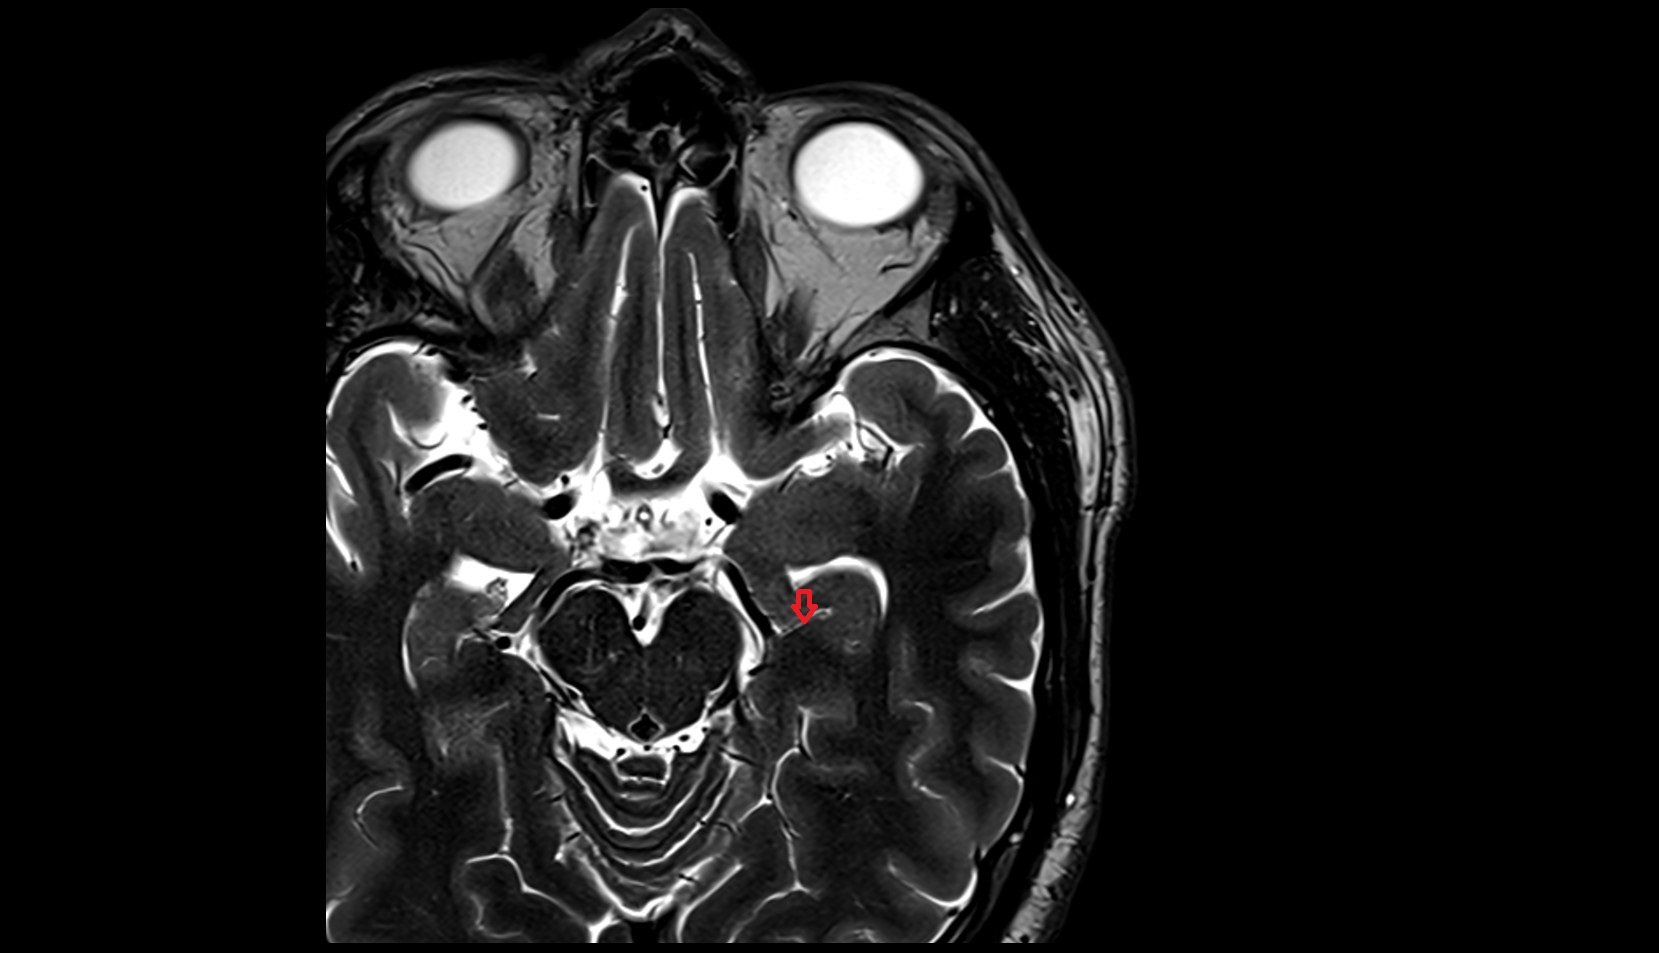

- Crural cistern